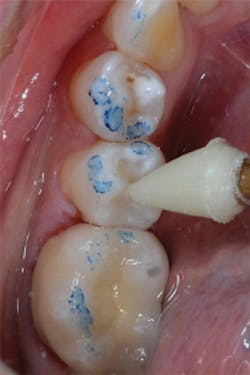

Figure 11: Preoperative view of teeth Nos. 4 and 5. The treatment plan includes composite restorations.

Figure 12: Final preparations on teeth Nos. 4 and 5. The Palodent Plus Sectional Matrix System has been used to isolate the MOD prep on tooth No. 4 and MO prep on tooth No. 5. The Palodent Plus Sectional Matrix System can be configured to restore multiple surfaces and multiple teeth in the same quadrant.